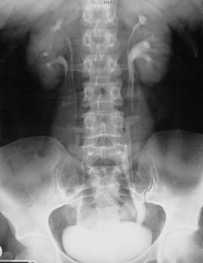

Под агенезией почки понимают ее одностороннее или двухстороннее отсутствие. Двухстороннее отсутствие почек относится к классическому синдрому Поттера, сочетается с другими аномалиями развития и несовместимо с жизнью. Встречается он с частотой 1 на 4000 новорожденных. Односторонняя агенезия отмечается с частотой 1 на 500 новорожденных. Чаще всего односторонняя агенезия является случайной находкой при лучевой диагностике , проводимой по разным причинам, в частности гипертензионном синдроме. Отсутствие почки может быть обнаружено уже при антенатальном УЗИ, отсутствует при этом и почечная артерия. При этом, как правило, отмечается компенсаторное увеличение контрлатеральной почки. Часто место отсутствующей почки занимает надпочечник, также увеличенный. Агенезию важно не спутать с эктопией, которая встречается намного чаще. Сочетание односторонней агенезии с аномалией протока Вольфа (эякуляторный проток) и кистой семенных пузырьков с той же стороны обозначают как синдром Циннера.

КТ, корональная реформация. Агенезия правой почки.